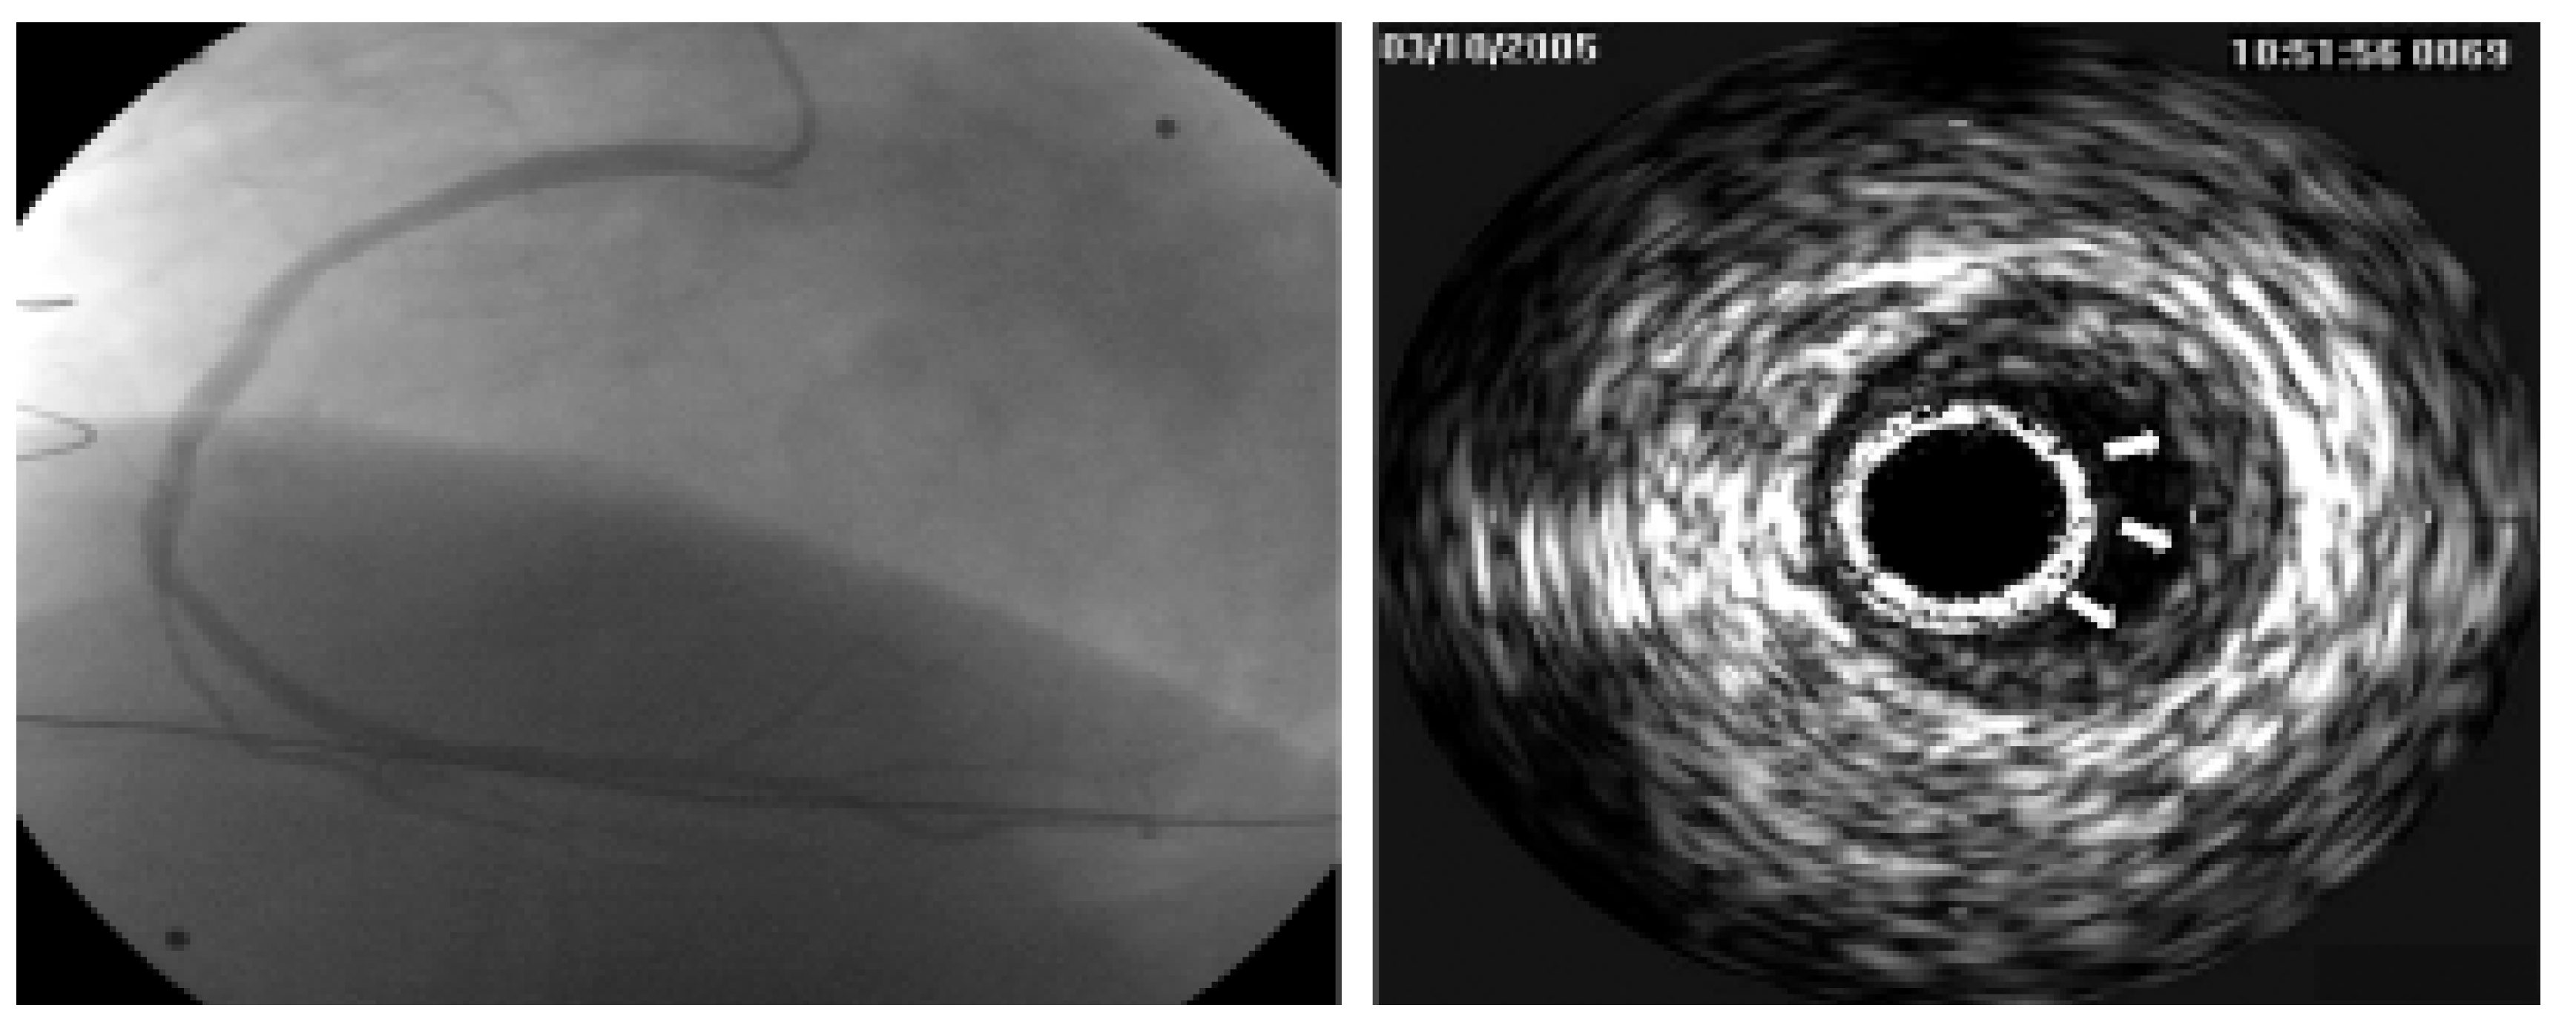

On September 23rd, 1985, a 34-year-old man with end-stage dilated cardiomyopathy of unknown origin and with history of severe dyspnea (NYHA III–IV) during the preceding five years underwent orthotopic heart transplantation (HTX). Left ventricular ejection fraction (EF) before HTX was 20%. Immunosuppression included cyclosporine A, azathioprine and prednisone. Acute cellular rejections occurred 14, 49 and 70 days after HTX. Six months after HTX the patient returned to full work as a farmer. The long follow-up was characterised by excellent quality of life, the lack of further rejections, severe infections and of secondary tumors. Twenty years after HTX, selective coronary angiography and intravascular ultrasound (IVUS) showed only mild coronary stenoses (Figure 1) associated either to de novo atherosclerotic lesions and/or graft vasculopathy. This surprisingly mild vasculopathy may be due to the excellent match (two HLA missmatch) with few cellular rejections in the very early course after HTX. EF was normal (60%). The major issue during follow-up was the appearance of moderate to severe renal function impairment probably related to a side effect of cyclosporine. Mild renal function impairment occurred few months after HTX with progressive severe deterioration of the creatinine clearance down to 27 ml/min/m2 twenty years after HTX. Renal biopsy, performed 20 years after HTX, showed typical changes with arteriolopathy characteristic for calcineurin inhibitor toxicity (cyclosporine) (Figure 2). This case illustrates how long-term survival after HTX is possible with excellent quality of life with only mild coronary vasculopathy and moderate to severe renal insufficiency.

Figure 1. The figure shows selective coronary-angiography of the right artery with the corresponding intravascular ultrasound (IVUS), both performed twenty years after cardiac transplantation. Coronary angiography and IVUS show mild stenoses (arrows) which may be associated with either graft vasculopathy and/or de novo atherosclerotic plaques. Left coronary artery (not shown in the figure) presented a similar pattern.